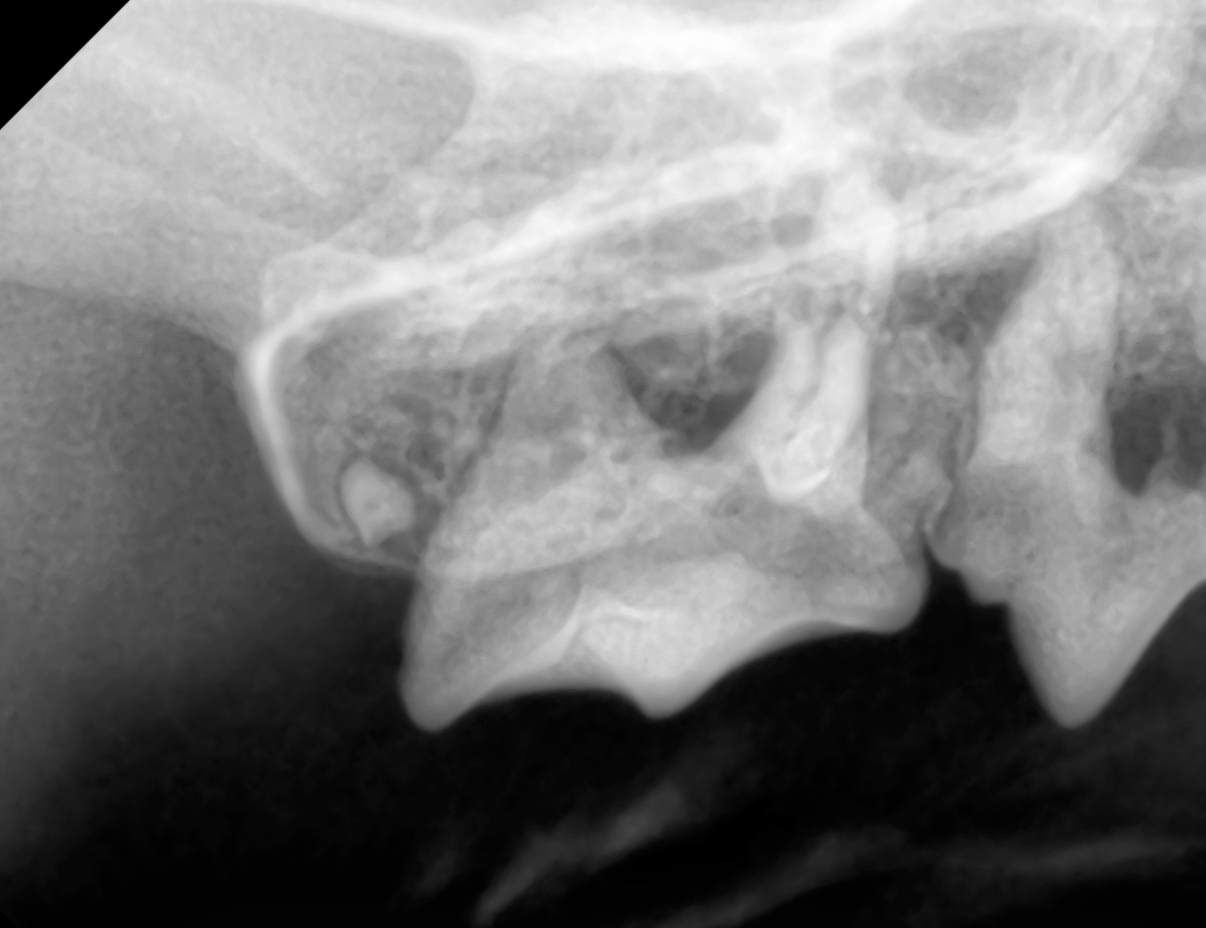

歯が本来の位置に生えてこず、顎の骨や歯ぐきの中に埋まったままになってしまう歯を「埋伏歯」といいます。

埋伏歯の周囲に液体がたまった袋(嚢胞)ができることがあります。

嚢胞はゆっくりと大きくなり、顎の骨を溶かしてしまったり、顎の腫れの原因になることがあります。

埋伏歯は、外から見るだけでは「歯がもともと無いのか」「歯が埋まっているのか」を区別することができません。

そのため、歯科用レントゲン検査を行うことで、顎の中に歯が残っていないか確認することがとても重要です。